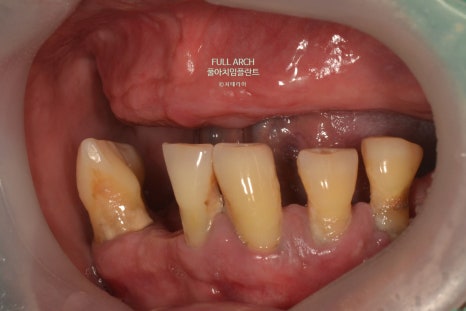

풀아치가 적합한 경우로는 다양한 복합적 치료가 불가능 하여 아래의 징후를 예를 들 수 있다.

잇몸질환으로 축적된 염증과 반복되는 감염으로 잇몸뼈를 상실한 경우

잇몸 퇴축으로 임플란트가 불가능한 경우

빠지거나 깨진치아가 여러개로 복합적인 문제들로 치료의 한계가 있는 경우